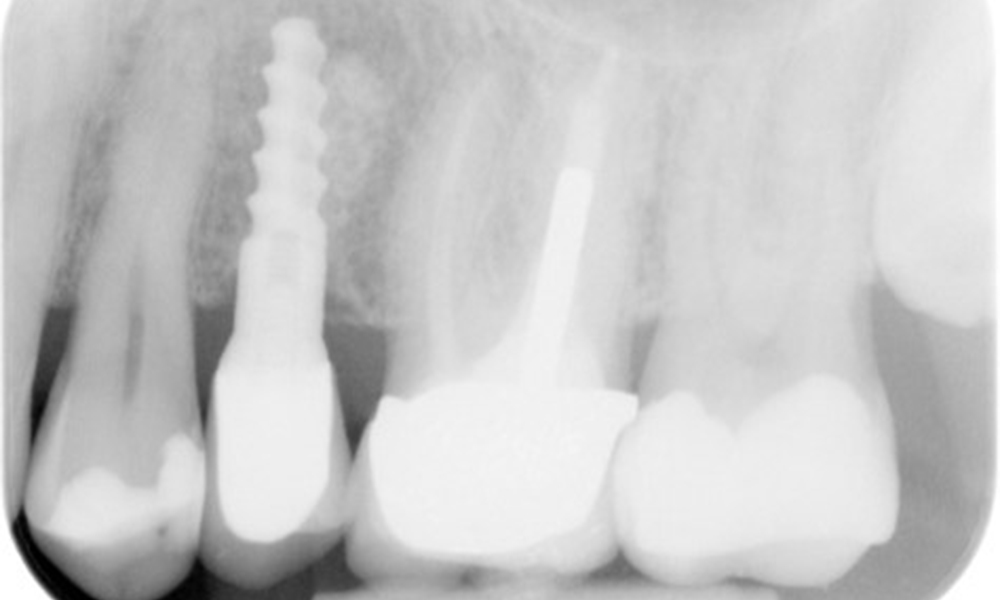

Zahnfilme (bzw. Bissflügelröntgen)

Zahnfilme (bzw. Bissflügelröntgen) aufgenommen am: 18.02.2021

Röntgenaufnahme zeigt Knochenabbau

Die Röntgenaufnahme zeigt den Knochenabbau.